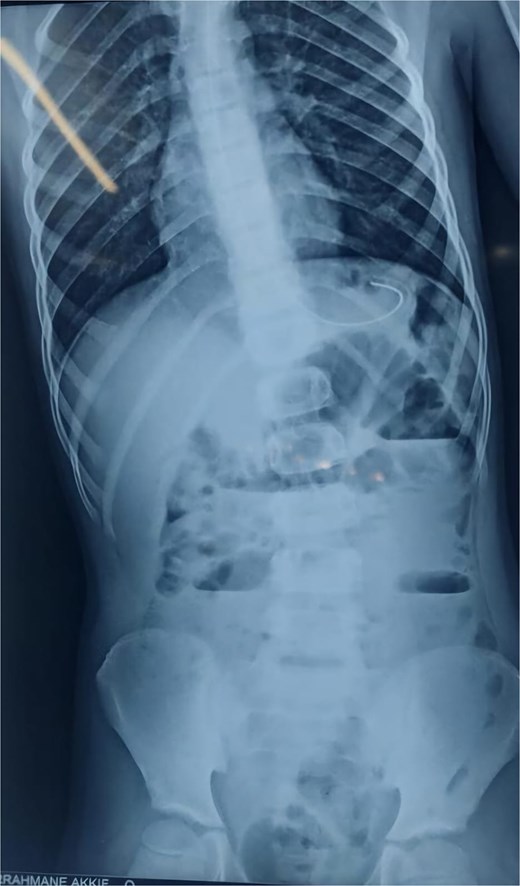

An abdominal X-ray showed multiple dilated bowel loops with air-fluid levels (Figs 1 and 2), consistent with a high-grade intestinal obstruction. Given the patient’s surgical history, a diagnosis of volvulus secondary to intestinal malrotation was strongly considered.

X-ray image after 6 h of admission, showing persistence of air-fluid levels.